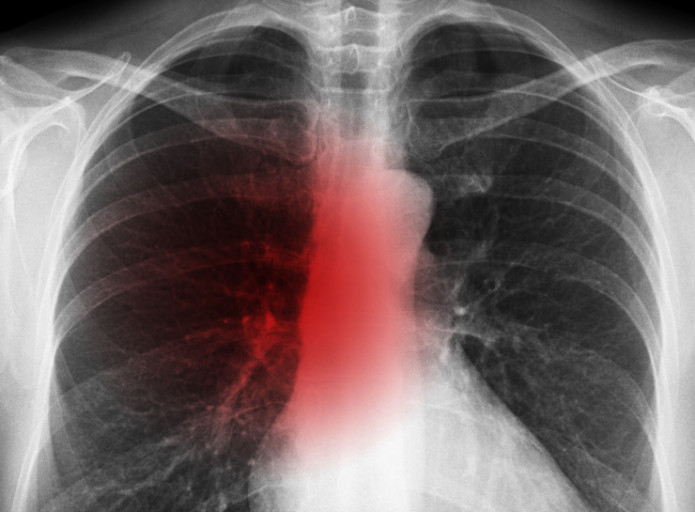

3. 호흡곤란

- 폐에 염증이 생겨 산소 교환이 제대로 안 되면 숨이 차고 호흡이 가빠짐

- 계단을 오르거나 조금만 움직여도 숨이 찰 수 있음

- 심하면 휴식 중에도 숨쉬기가 힘들어지고 청색증(입술, 손끝이 파래짐) 발생

폐렴 증상 4. 흉통(가슴 통증)

- 폐렴으로 인한 염증이 흉막까지 퍼지면 날카로운 가슴 통증이 발생

- 숨을 깊게 들이쉴 때나 기침할 때 통증이 심해지는 특징